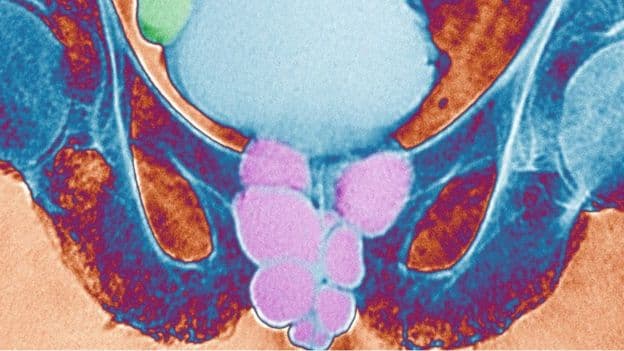

Ища в Интернете подсказки, я понял, что я не одинок. Хронический небактериальный простатит является наиболее распространенным типом простатита (воспаление предстательной железы). Также известный как «синдром хронической тазовой боли» (СХТБ, CPPS), он, по оценкам, затрагивает около 8% мужчин.

Парк, после прочтения о терапии для CPPS, разработанной американскими медиками в Стэнфордском университете, пришел к выводу, что боль вызывается напряжением: беспокойство часто сохраняется в мышцах, и мускулатура таза особенно уязвима, поскольку она переплетена с нервами. Решение состояло в том, чтобы успокоить беспокойный ум.